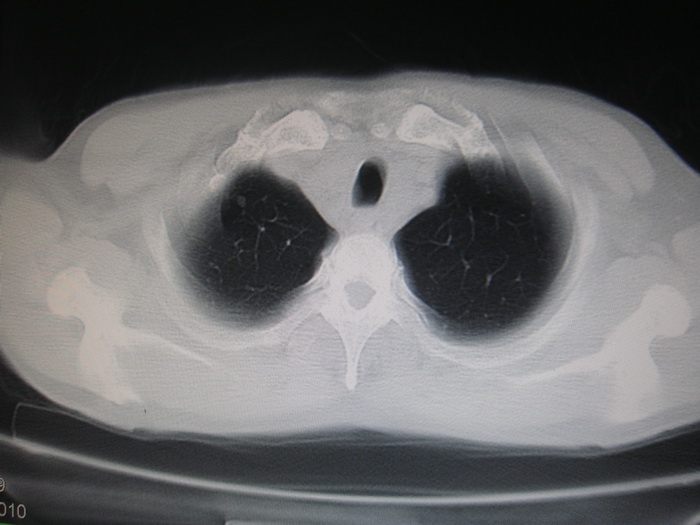

标题: CT28366:男性,45岁,偶尔发现右颈部肿块行胸部CT扫描。 [打印本页]

男性,45岁,偶尔发现右颈部肿块行胸部ct扫描。

两肺多发结节灶及纵膈淋巴结肿大考虑为转移

两肺多发性转移瘤,纵隔淋巴结转移。

两肺多发性转移瘤,纵隔淋巴结转移。食道中上段管壁似乎增厚,作相关检查。